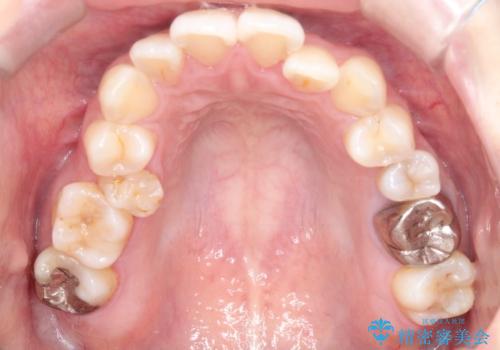

【ワイヤー矯正】口元を下げたい、下の歯の凹凸を無くしたい

- 主訴:口元を下げて前突感を無くしたい、下の歯の凹凸も無くしたい

右側第二小臼歯、左側第一小臼歯、下顎両側第一小臼歯を抜歯しワイヤ-矯正を行いました。

骨格的顎の変位を認めたため、顔貌に対しピッタリ上下の歯の正中を合わせることは難しいと説明し、上下左右計4本小臼歯を抜歯しワイヤー矯正治療を行いました。